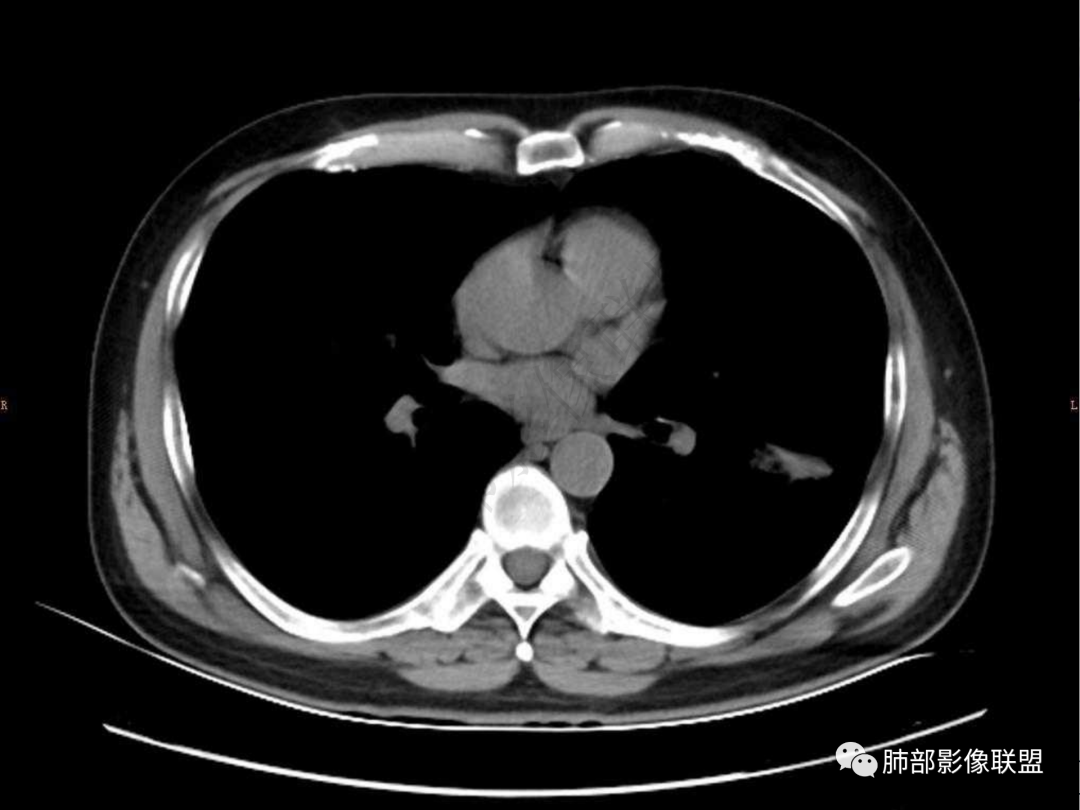

1.中年男性,咳嗽咳痰20余天,间断咯血2周

2.左肺下叶团片影,跨背段及内前基底段,实性部分类椭圆形,密度不甚均匀,可见毛刺及棘状突起,未见典型分叶及胸膜凹陷。病灶上下缘可见相应肺段支气管旁进侧出,管壁轻度增厚,未见狭窄阻塞。

3.周边较大范围磨玻璃影,边界相当模糊,小叶增厚明显。注意叶裂另一侧、左肺舌段亦可见磨玻璃影及增厚的小叶间隔。未见明确卫星病灶。

4.实性部分不均匀环形强化并显示一小范围低密度坏死区或空洞。较之肺窗,整体纵隔窗范围较小,提示病灶并不十分密实。抑或为不同时段图像。

5.双肺门及纵隔未见增大淋巴结。未见胸腔积液。